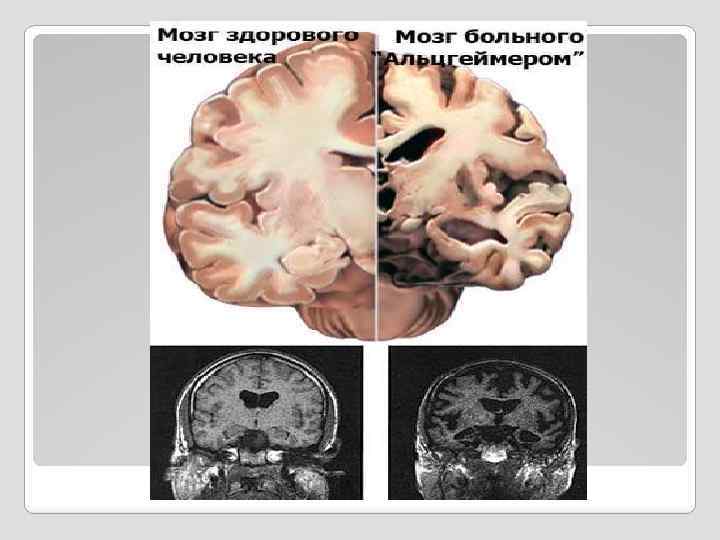

Изменения в головном мозге подтверждающие диагноз болезни Альцгеймера, в основном выявляют в наружном слое мозга (коре) и гиппокампе, который залегает в глубине полушарий и играет важную роль в процессах памяти. При микроскопическом исследовании этих областей мозга обнаруживаются нейрофибриллярные клубочки и нейритические бляшки. Клубочки состоят из патологически измененных нейронов, содержащих аномальные белки. Бляшки представляют собой участки отложений в межклеточном пространстве белковоуглеводных комплексов – амилоида. Чем больше в мозгу клубочков и бляшек, тем сильнее выражены интеллектуальные нарушения.